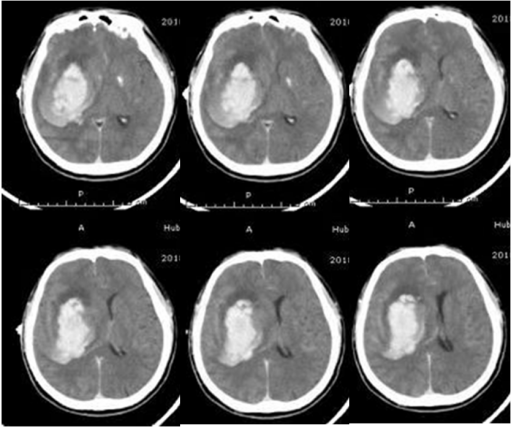

术前 术后3天

锥颅软通道置管引流具有微创、操作方便、血肿清除率高的优点